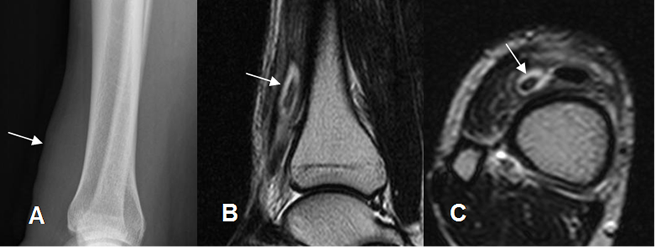

Fig 212. Cuerpo extraño.

A: Rx lateral. Prominencia de los tejidos blandos en la parte anterior de la pierna.

B: RM sagital y C: RM axial en T2. Imagen hipointensa y rodeada por líquido, que corresponde a cuerpo extraño de madera.